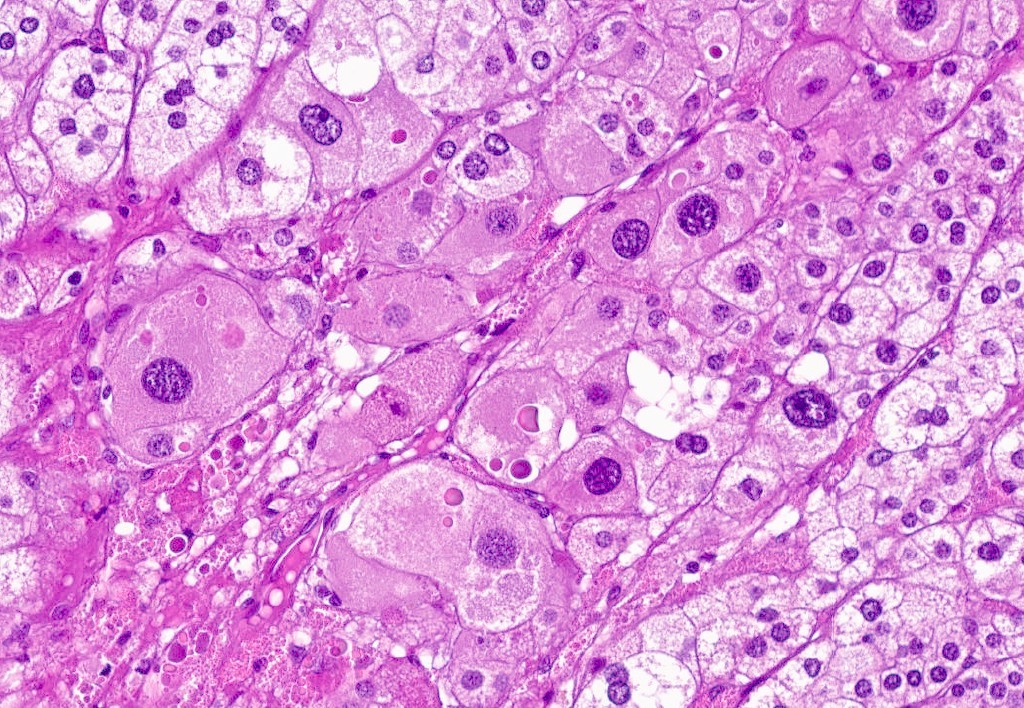

Microscopic (histologic) description

- In comparison to surrounding adrenal gland, adenoma cells are larger with different cytoplasm, increased variation in nuclear size

- Distinct cell borders, cells have abundant foamy cytoplasm reminiscent of zona fasciculata

- Balloon cells: clusters of cells with enlarged lipid-rich cytoplasm (seen in Cushing syndrome)

- Histologic variants: oncocytic, myxoid

Microscopic (histologic) images

Contributed by Xiaoyin "Sara" Jiang, M.D., Debra Zynger, M.D., @Andrew_Fltv on Twitter and @SueEPig on Twitter